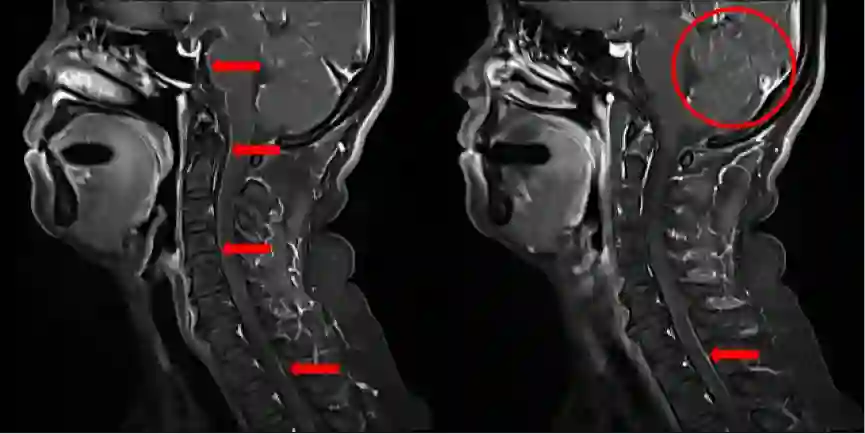

患者于2018年9月27日因“剧烈头痛伴呕吐”就诊于我科——郑州大学附属第一医院肿瘤科,查体急性病容,表情痛苦,神志清楚,脑膜刺激征可疑阳性,考虑脑膜转移性可能性大,故立即行腰椎穿刺,提示颅内压400mmH2O,并行脑脊液细胞学检查 ,未见肿瘤细胞。但是结合患者症状体征仍不能排除脑膜转移可能。故行颈椎增强MRI排除其他部位脑脊液转移可能,检查结果提示颈椎增强MRI可见脑脊膜多发转移(图6)。

图6. 颈椎增强MRI提示脑脊膜多发转移影像

2018年9月29日,患者病情出现恶化,出现头痛伴短暂性意识障碍,查体双侧瞳孔等大等圆,对光反射灵敏,心率45次/分,血压160/100mmHg,考虑颅内高压导致出现Cushing反应。立即予以镇静、脱水等对症处理,并紧急腰穿行脑脊液引流,同时鞘内注射培美曲塞化疗联合全身培美曲塞单药化疗。患者于2018年9月30日恢复意识,并能交流顺畅,活动自如。同日,患者开始口服靶向阿来替尼二线治疗,并于10月2日因头痛再次腔内注射培美曲塞单药化疗。后患者肺部和中枢神经系统控制可,患者PS评分恢复0分。从治疗的结局来看,该病例算是一例非常成功的脑膜转移治疗成功的病例。

图7.治疗后复查患者颈椎核磁影像